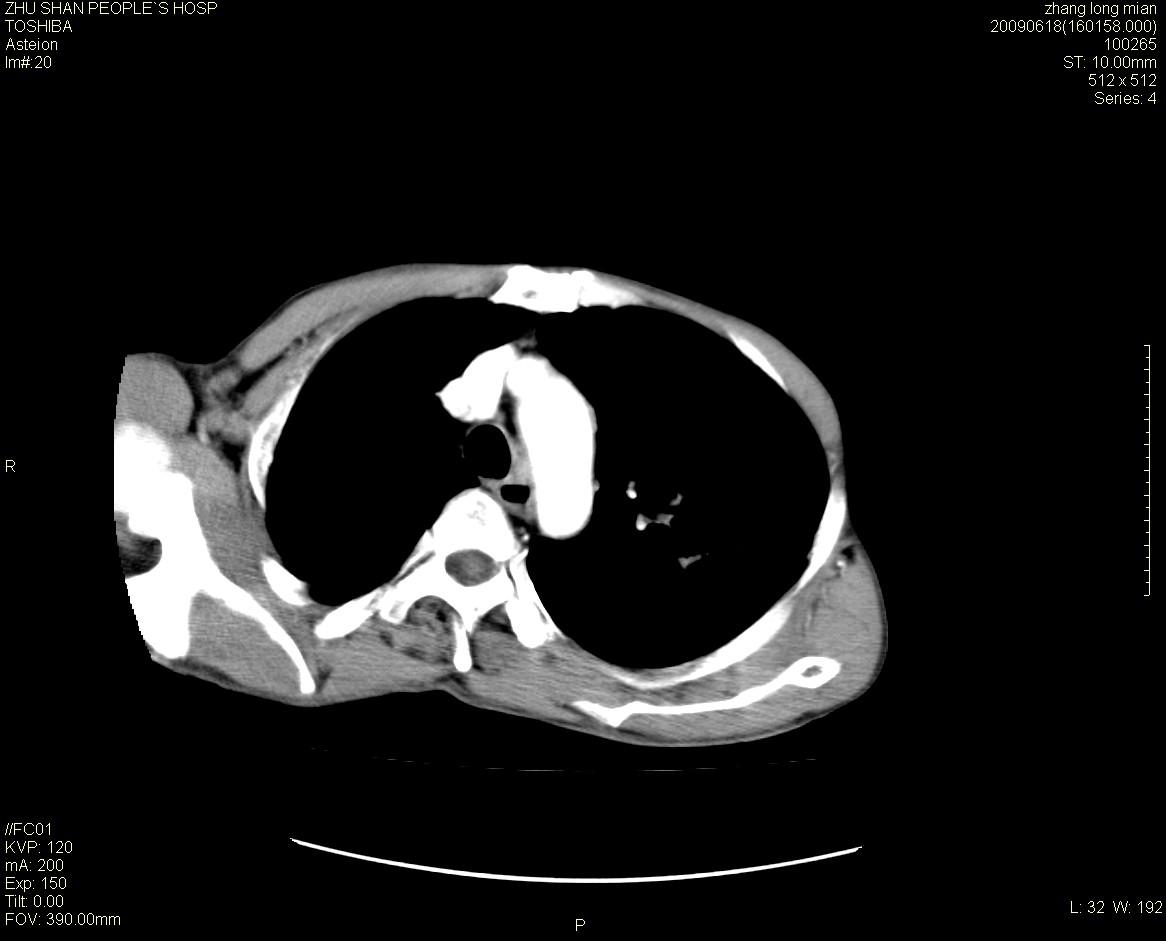

男性 65岁 胸片发现右下肺包块.诊断肺ca并纵隔转移没有问题吧!

两侧胸廓不对称,右侧呈塌陷改变,右肺萎缩。

右下肺见浅分叶状软组织块影,边缘有毛刺,其下部似见不完整偏心空洞影,邻近胸膜凹陷征,并胸腔积液。

增强见纵隔区气管隆突上下及左肺门区肿大淋巴结。左肺感染性病灶。

另见右上肺见一枚小结节影,性质待定。